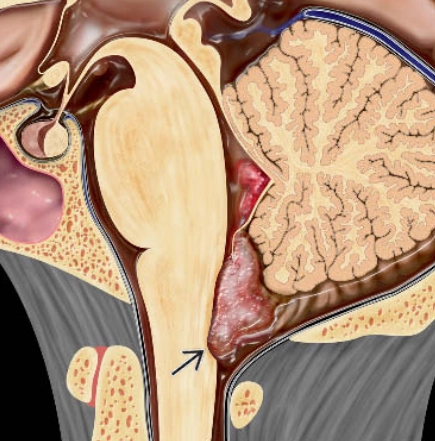

• U dưới màng não thất (Subependymoma)

• U màng não thất (Ependymoma- EPN)

• U màng não thất trên lều (Supratentorial Ependymoma- ST-EPN)